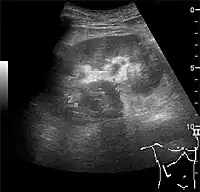

Hydronephrosis

One of the primary indications for referral to US evaluation of the kidneys is evaluation of the urinary collecting system. Enlargement of the urinary collecting system is usually related to urinary obstruction and can include the pelvis, the calyces and the ureter. Hydronephrosis is seen as an anechoic fluid-filled interconnected space with enhancement within the renal sinus, and normally, the dilated pelvis can be differentiated from the dilated calyces.[1]

Several conditions can result in urinary obstruction. In both adults and children, masses, such as abscesses and tumors, can compress the ureter. In children, hydronephrosis can be caused by ureteropelvic junction obstruction, ectopic inserted ureter, primary megaureter and posterior urethral valve (Figure 13). In the latter, both kidneys will be affected. In adults, hydronephrosis can be caused by urolithiasis, obstructing the outlet of the renal pelvis or the ureter, and compression of the ureter from, e.g., pregnancy and retroperitoneal fibrosis. Urolithiasis is the most common cause of hydronephrosis in the adult patient and has a prevalence of 10%–15%.[1]

The hydronephrosis is typically graded visually and can be divided into five categories going from a slight expansion of the renal pelvis to end-stage hydronephrosis with cortical thinning (Figure 15). The evaluation of hydronephrosis can also include measures of calyces at the level of the neck in the longitudinal scan plane, of the dilated renal pelvis in the transverse scan plane and the cortical thickness, as explained previously (Figure 16 and Figure 17).[1]